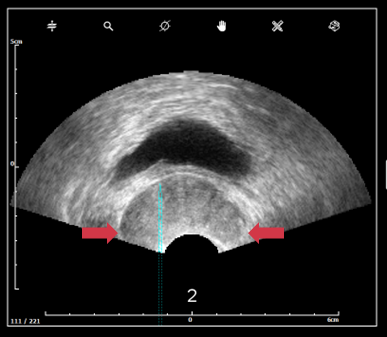

c. Probe pressure and probe troubles

- Lobes exceed ultrasound image → gland deformation due to excessive pressure on the prostate.

-

Prostate must be clearly visible, no black continuous line should appear. If you suspect a bad image quality, read this article.